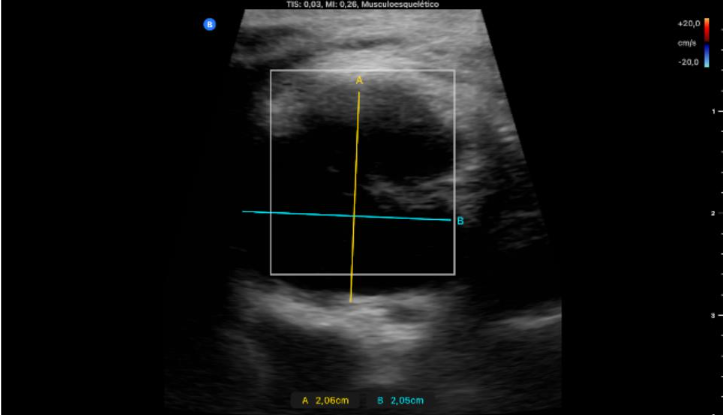

Objetivación de conglomerado adenopático con 2 adenopatías predominantes redondas de 2 cm, bien delimitadas, con hilio periférico y vascularización en hilio. Tiroides normal, bazo e hígado normales sin LOEs.

Uso de sonda lineal, proyección transversal: adenopatía redondeada con hilio periférico bien delimitada que no capta Doppler; y longitudinal: varias adenopatías, 2 de ellas más grandes, donde se objetiva la vascularización limitada al hilio.